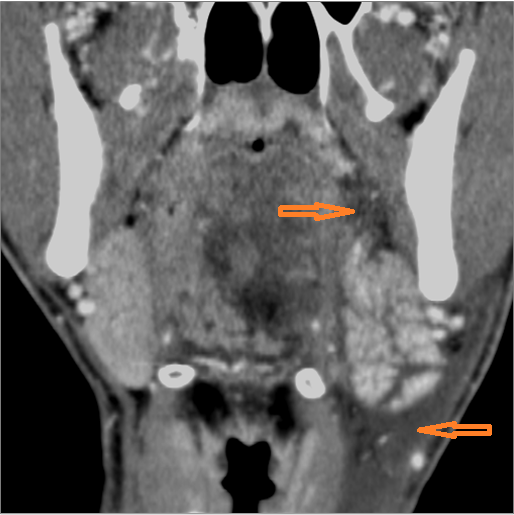

There is edema within the adjacent deep neck, retropharyngeal and/or prevertebral spaces

There is abscess within the adjacent deep neck, retropharyngeal and/or prevertebral spaces.

There is evidence of active extravasation from an arterial source